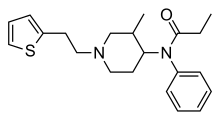

Anilidopiperidines

- 3-Allylfentanyl

- 3-Methylfentanyl

- 3-Methylthiofentanyl

- 4-Phenylfentanyl

- Alfentanil

- α-Methylacetylfentanyl

- α-Methylfentanyl

- α-Methylthiofentanyl

- Benzylfentanyl

- β-hydroxyfentanyl

- β-hydroxythiofentanyl

- β-Methylfentanyl

- Brifentanil

- Butyrfentanyl

- Carfentanil

- Fentanyl

- Lofentanil

- N-Methylcarfentanil

- Mirfentanil

- Ocfentanil

- Ohmefentanyl

- Parafluorofentanyl

- Phenaridine

- R-30490

- Remifentanil

- Sufentanil

- Thenylfentanyl

- Thiofentanyl

- Trefentanil

Structures